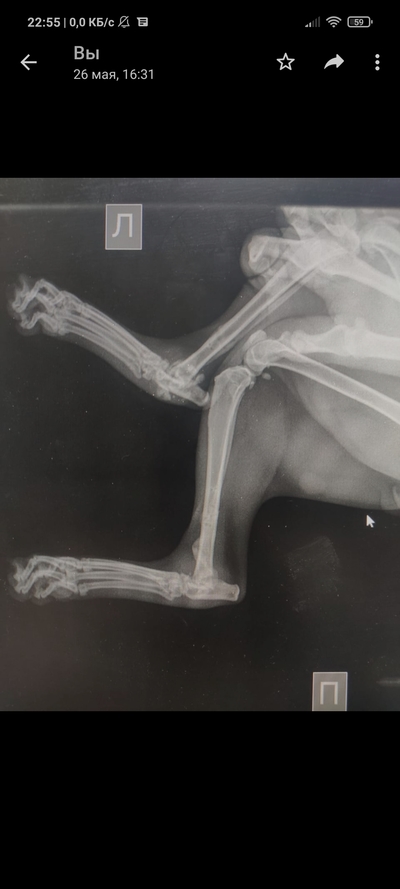

Так уж получилось что я ветеринарный врач, работаю в интенсивной терапии - принимаю и лечу самых тяжелых животных. На днях ближе к ночи прибегает женщина с котом, который шлёпнулся перед ней на улице. При осмотре выясняется что кот в шоке - лежит на боку, без давления, температуры, у него сломаны передние лапы, лицо, пневмоторакс и немного жидкости в брюшной полости (вероятно кровь). Женщина оставляет двадцатку на первые сутки и идет искать хозяина, кот помещается в стационар для стабилизации состояния. Всю ночь я ебусь с этим котом, вывожу его из шока, спускаю ему пневмоторакс, грею, обезболы льются рекой, к утру кот похож на кота, а не на покойника - начал садиться, ползать, полизал еду.

В общем, четвертый день от падения, полет нормальный, кот начал есть сам, а я иду на смену, ждите новостей, думаю скоро будет пост про то, как мы оперируем животных, в частности собираем ходули герою этой истории 😁